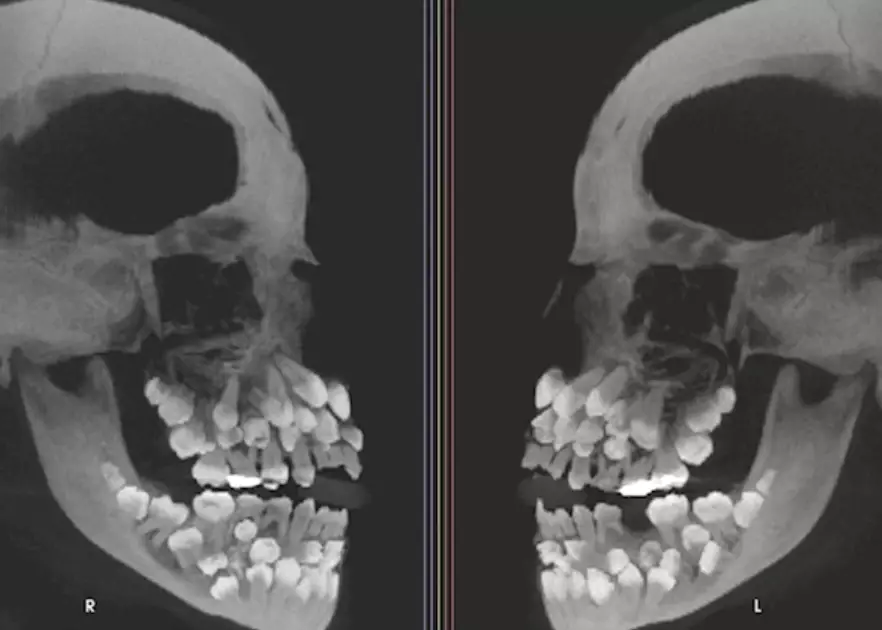

據外媒報導,這位來自巴西米納斯吉拉斯州(Minas Gerais)的女孩,原本想拔一顆上排的乳牙,但X光顯示她口中藏有18顆乳牙、32顆恆牙,以及31顆多生牙,總共高達81顆。

一般成人正常牙齒數為32顆

一般成人正常牙齒數為32顆,而超出正常數量的額外牙齒被稱為「多生牙」,通常多生牙數只有1至2顆,如此多多生牙的情況極為罕見。多生牙通常隱藏在牙齦內,可能干擾正常牙齒排列,甚至導致其他問題如囊腫等。

這個病例由巴西胡伊斯迪福拉聯邦大學(Universidade Federal de Juiz de Fora)牙科醫院研究團隊發表在《美國牙齒矯正與口腔顎面外科學會雜誌》(American Journal of Orthodontics and Dentofacial Orthopedics,AJO-DO),研究團隊透過精密影像檢查牙齒位置,並進行基因檢測,以確定是否與遺傳疾病有關。

染色體檢查結果顯示,這名女孩患有一種罕見的遺傳變異,但該變異與多生牙的直接關聯性尚未確定。部分多生牙深埋在牙齦內或外觀與正常牙齒相似,貿然拔除可能損害顎骨,為降低風險,研究團隊召集牙齒矯正科、口腔顎面外科、牙周病科和假牙科等多科醫生,共同制定長期治療計畫,以保護女孩口腔健康和未來牙齒排列。